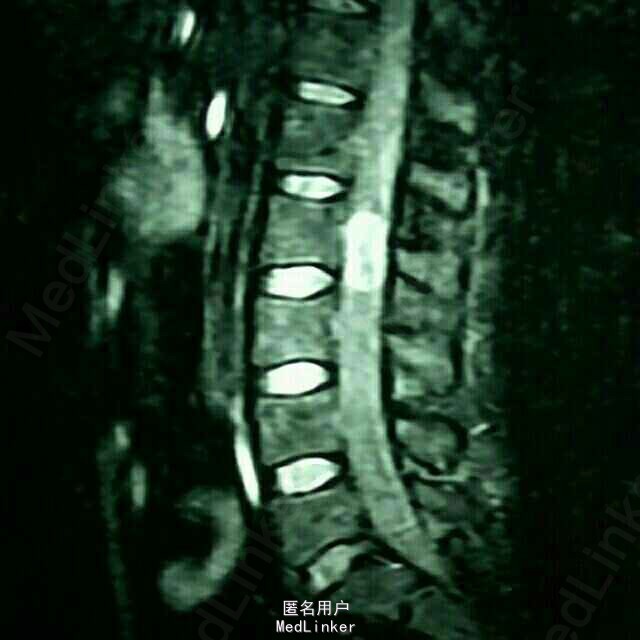

患者四肢肌力及肌张力可,病理反射未引出;鞍区及左侧大腿疼痛,无感觉减退。 腰椎MRI:腰2椎管内占位病变

患者四肢肌力及肌张力可,病理反射未引出;鞍区及左侧大腿疼痛,无感觉减退。 腰椎MRI:腰2椎管内占位

腰2神经鞘瘤 患者在全麻下行腰2椎管内占位病变切除术,术中见病变位于腰2神经马尾,呈囊实性,分界清,包裹神经纤维

术后病理提示:神经鞘瘤 神经鞘瘤为良性肿瘤,切除后可有效接触肿瘤占位效应,但神经被瘤体包裹,患者术后会出现左腿麻木症状,已逐渐好转,嘱3月后复查。